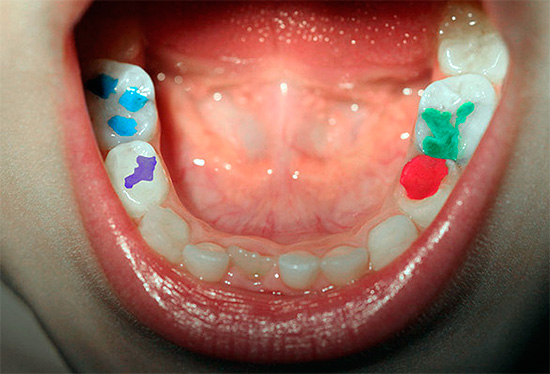

La scelta del trattamento dipende non solo dallo stadio di sviluppo della malattia, ma anche dall'età del paziente, dalla posizione della cavità, dai requisiti di estetica del materiale di riempimento. Ad esempio, la pratica ha dimostrato che i bambini che sanno cosa sono le otturazioni colorate e competono tra loro nella loro luminosità, tollerano con molta pazienza e pazienza le manipolazioni con i denti per ottenere un riempimento così luminoso.

nota